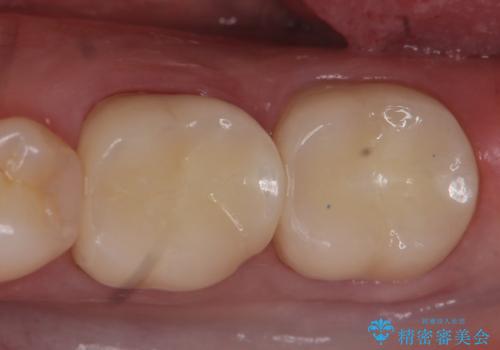

左下6、7番目の歯に根尖病変を認めたため、再根管治療後、オールセラミッククラウンによる補綴を行いました。

今回用いたオールセラミッククラウンは、ジルコニアフレームという白い素材の上にセラミックを盛っているため審美性が非常に高いのが特徴です。

またジルコニアは人工ダイヤモンドの材料にも使われているほど高い強度を持っており、そのためオールセラミッククラウンは審美性だけでなく、奥歯やブリッジの補綴も可能とするクラウンです。